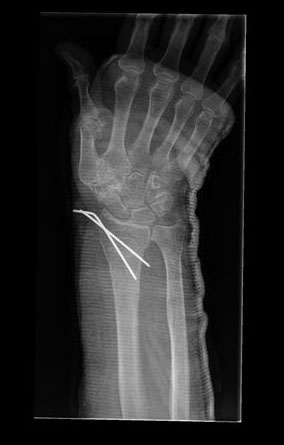

Tratamiento de fractura de radio con agujas.

Tratamiento con agujas de fractura de radio.